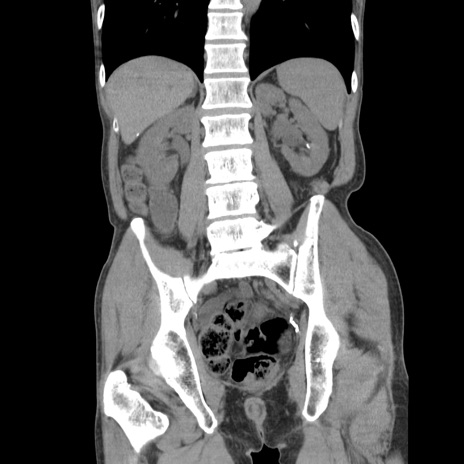

症例11(冠状断像)

【症例】 60歳代男性

【主訴】 下腹部痛

【現病歴】 本日夜中より下腹部痛の症状認め、受診。

【既往歴】 膀胱癌(膀胱全摘+尿管皮膚瘻術) 、胃癌術後

【身体所見】 BT 35.3℃、PR 58/min、BP 136/98mHg、腹部平坦、軟、腸蠕動音±、ストマ留置あり、左上腹部~正中部に圧痛あり、反跳痛なし。

【データ】WBC 5100、CRP0.01